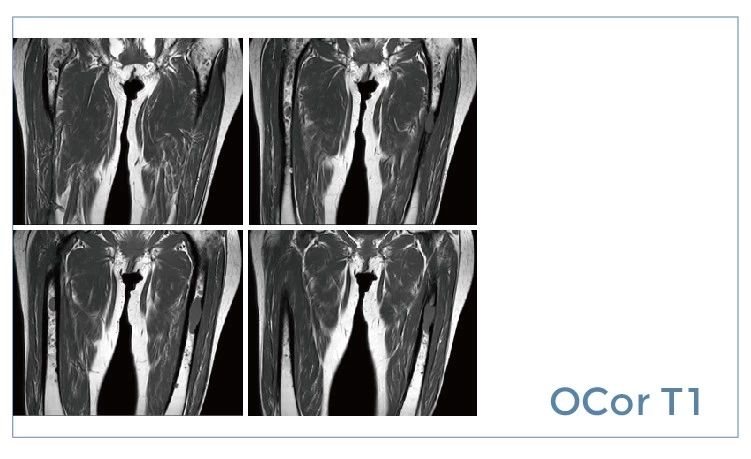

【朗润影像档案】20190712磁共振影像病例结果讨论